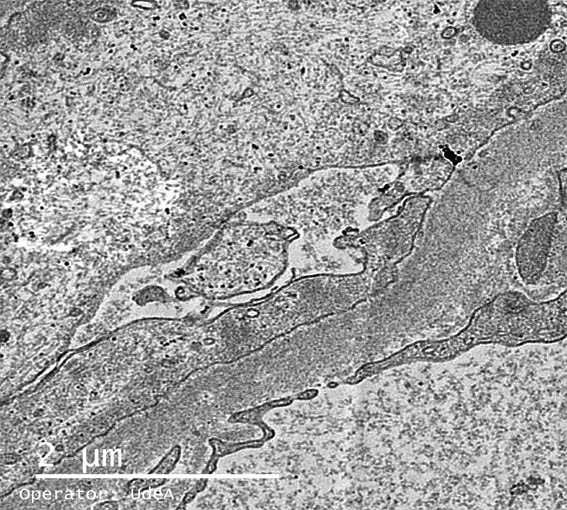

Figura 11. Microscopía electrónica, X8.000.